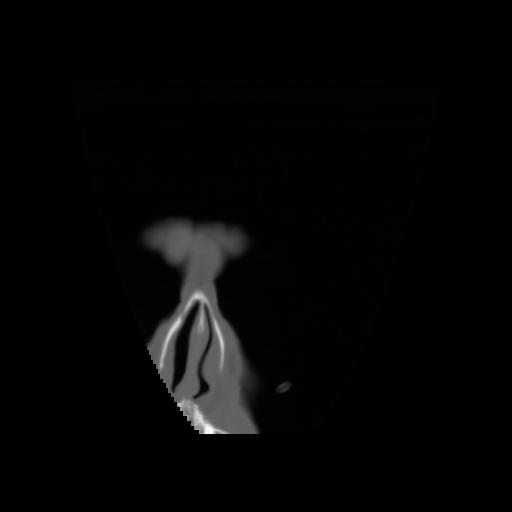

5 CEREBRO,,Coronal,3.000,CEREBRO,Coronal,